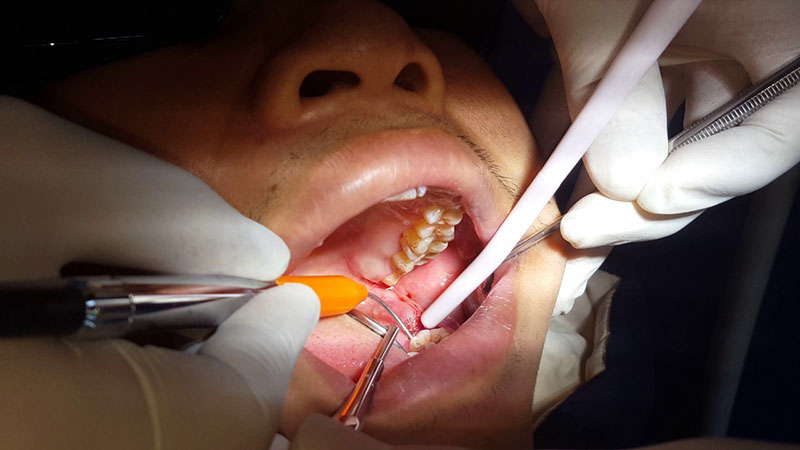

Thăm khám cấu trúc răng cần nhổ và kiểm tra sức khỏe răng miệng

Bác sĩ sẽ tiến hành thăm khám, chụp X – Quang để xác định hình dạng, vị trí và tình trạng xương xung quanh vị trí răng cần nhổ. Từ đó, bác sĩ ước tính mức độ khó của ca tiểu phẫu và hướng nhổ răng hợp lý nhất.